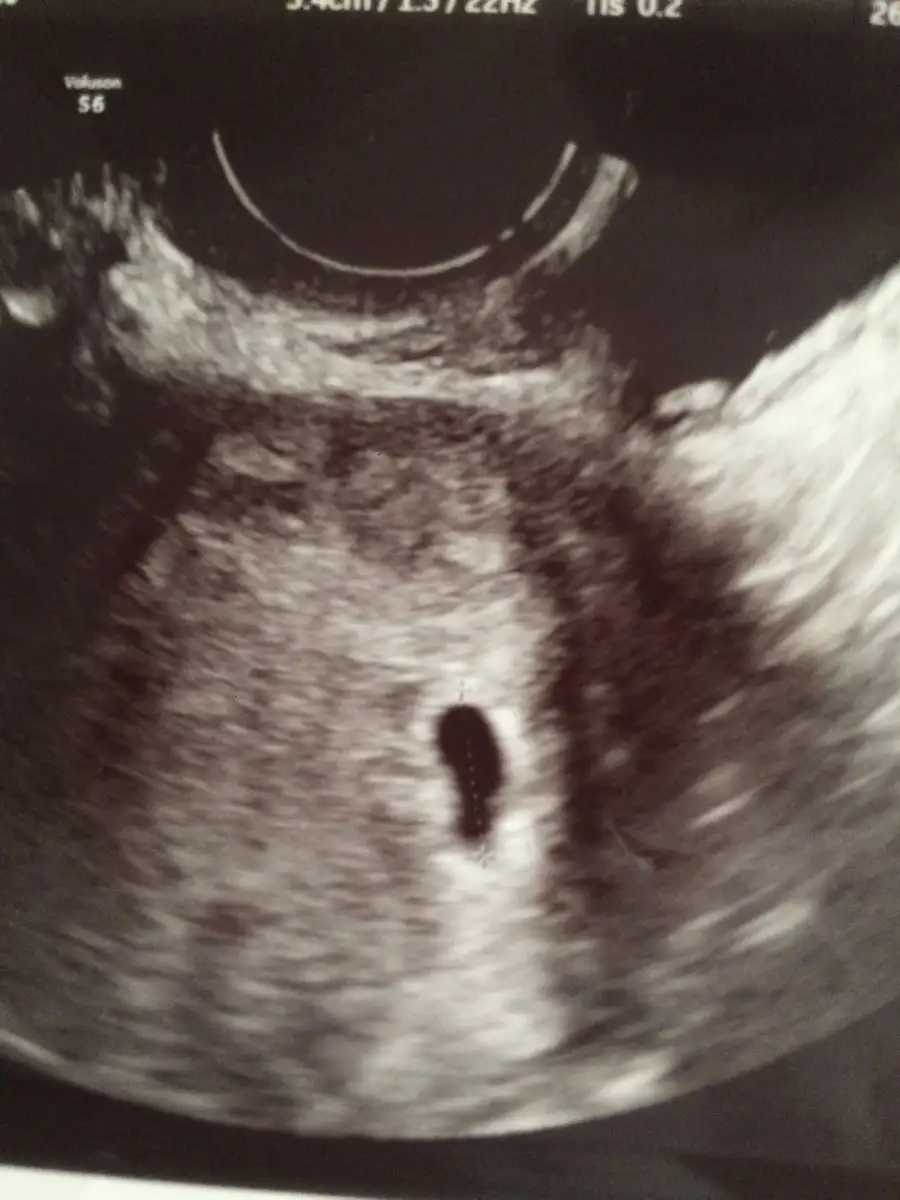

yani boş gebelikten mi şüphelendi ?Eki Görüntüle 2219153 Kese bu şekilde kızlar 11 mm dedi sanırım yanlış anlamadıysam

Yok cnm boş gebelikten şüphelenmedi..ama kese yapısından sağlıksız olma ihtimali olabilir dedi..ama düzelebilir de sesi boş gebelik demesi için zaten henüz erken..yani boş gebelikten mi şüphelendi ?

Eki Görüntüle 2219153 Kese bu şekilde kızlar 11 mm dedi sanırım yanlış anlamadıysam

bana da 2.2 mm dedi.. ovülasyonum 2 aralık.. 5 haftalık hamilelik.. benim ki bayağa minik o zamanEki Görüntüle 2219153 Kese bu şekilde kızlar 11 mm dedi sanırım yanlış anlamadıysam

Benimde kafamı karıştıran kese şekli oldubana da 2.2 mm dedi.. ovülasyonum 2 aralık.. 5 haftalık hamilelik.. benim ki bayağa minik o zaman